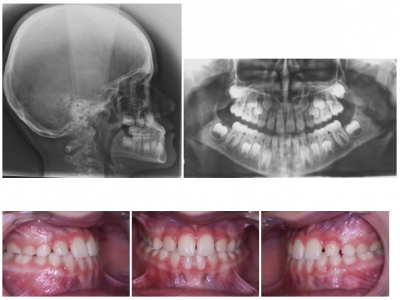

- Le premier cas est celui d’une petite fille antillaise de 5 ans 8 mois, présentant un articulé croisé global de toute l’arcade (Fig. 1). Le maxillaire est insuffisamment développé dans le sens antéro-postérieur et dans le sens transversal, sans aucune déviation latérale de la mandibule, le recouvrement est inversé mais normal en quantité. Elle est en denture lactéale, sans aucun diastème, les dents inférieures sont versées lingualement pour tenter de compenser le décalage. Il y a une hérédité dans toute la famille paternelle (Fig. 2).

La téléradiographie montre la classe III squelettique et sur la radiographie panoramique on note un manque de place pour les dents définitives aux 2 arcades (Fig.3-9). 15 et 25 peu visibles à ce stade, ont un retard de minéralisation.

- Pour le premier cas, à l’arcade maxillaire nous avons posé un appareil comportant des surélévations molaires et des vérins d’expansion (Fig. 4). Les surélévations postérieures sont la clé du traitement, elles recouvrent les faces palatines et occlusales des dents situées derrière les canines.

Quand le recouvrement par les incisives centrales est obtenu, les cales sont progressivement meulées puis la plaque est supprimée (Fig. 5).

Afin de conserver le résultat acquis, comme contention transitoire, les dernières molaires de lait sont surélevées, et 11 et 21 sont allongées.

La patiente est revue en denture permanente pour terminer le traitement (Fig. 6), on observe que le sens antéro-postérieur est mieux maintenu que le sens transversal, le côté droit est en articulé inversé de 15 à 12.

Le traitement est fini en multi-attaches auto-ligaturant passif (Fig. 7).

Dans le 1er cas, en observant les téléradiographies de profil, on note que bien que les incisives centrales supérieures soient en proalvéolie à la fin de la première phase de traitement (Fig. 8), comme l’occlusion normalisée est obtenue précocement (au moment de l’éruption des incisives), la croissance améliore spontanément leur inclinaison par le redressement des racines (Fig. 9).

L’obtention précoce d’une occlusion fonctionnelle, permet à la croissance de continuer d’améliorer les résultats acquis.